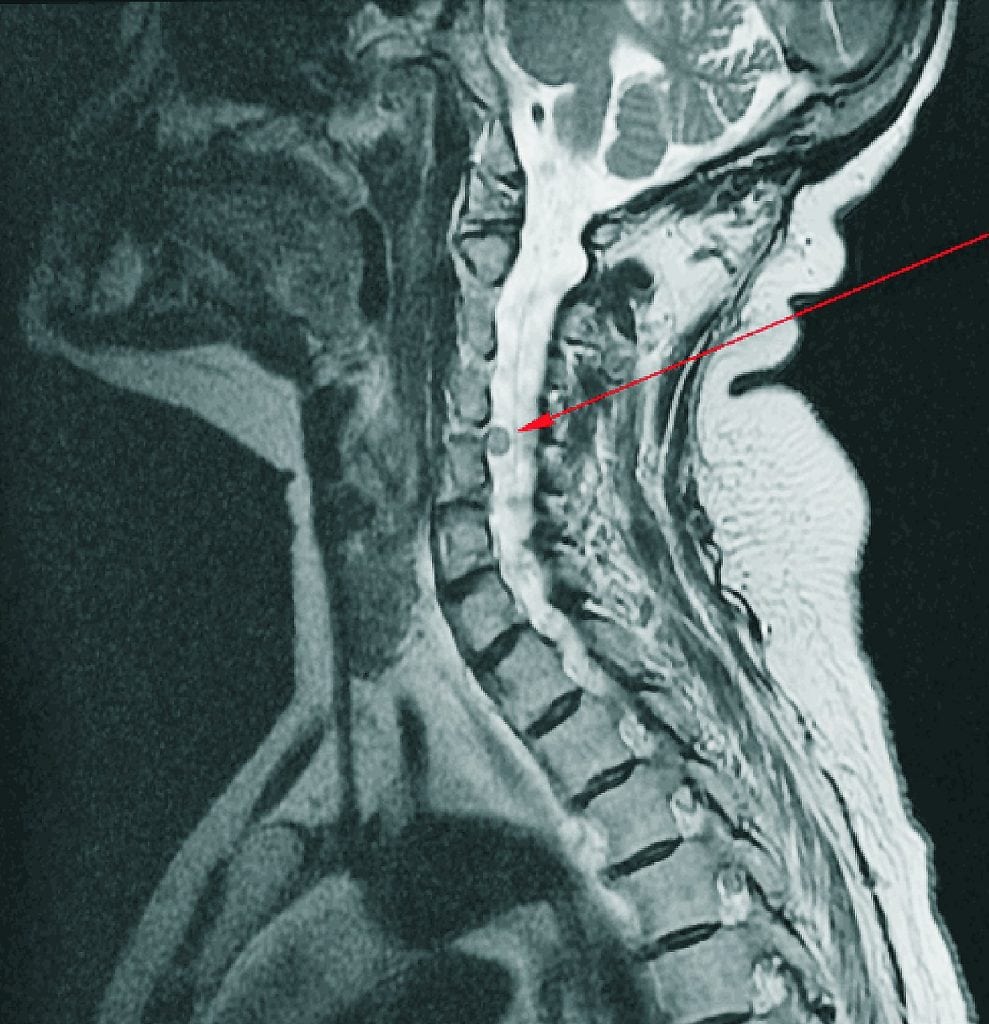

Грыжа в шейном отделе формируется при смещении фиброзного кольца, его разрыва и последующего вытекания пульпозного ядра.